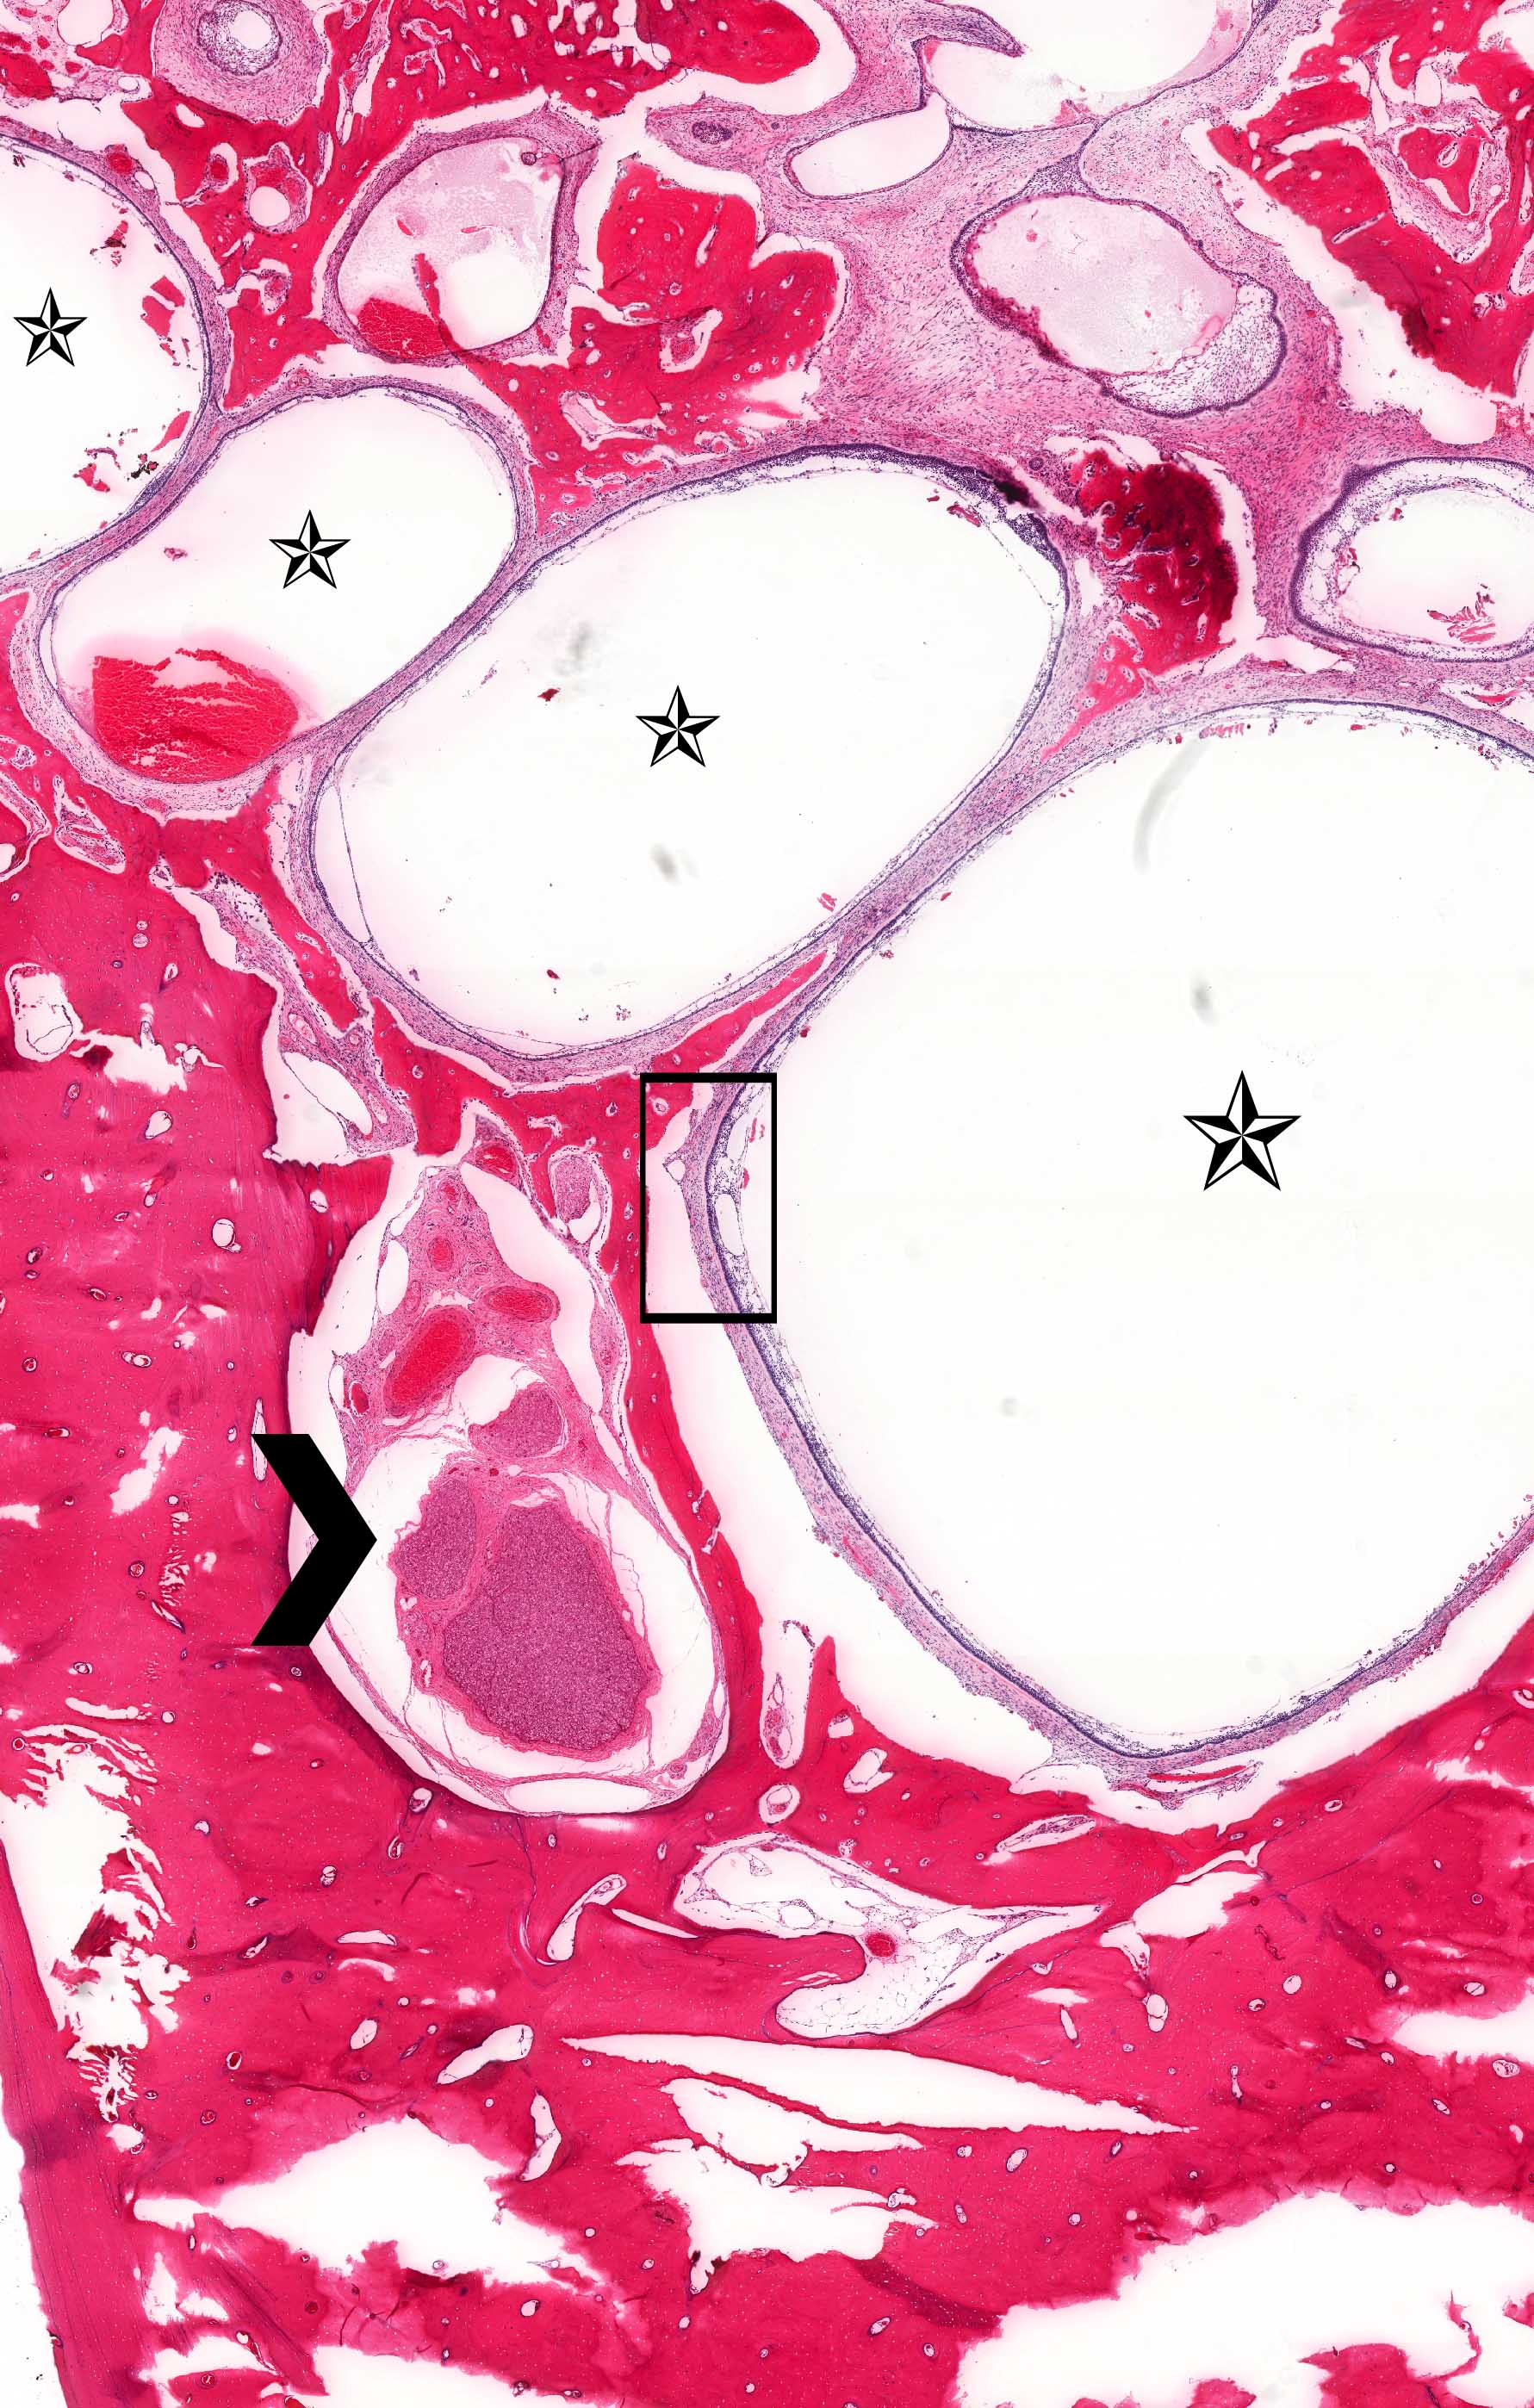

Microscopic (histologic) images

Contributed by Kelly Magliocca, D.D.S., M.P.H. and Anne C. McLean-Holden, D.M.D., M.S.

- Ameloblastoma, unicystic type:

- If surgically removed by enucleation, very little bone may present

- Evaluation of margins precluded by enucleation or curettage type of treatment

- When resected for margins with surrounding bone, unicystic gross appearance is conspicuous and may contain red-brown fluid

- If no mural growth identified on representative sections, consider submitting entire lesion

- Ameloblastoma, unicystic type has 3 histopathological patterns

- Single cystic lesion lined by ameloblastic epithelium that shows typical features of ameloblastoma in some areas, including columnar basal cells in palisading arrangement with vacuolated cytoplasm, hyperchromatic nuclei polarized away from basement membrane

- Suprabasal cells loosely textured and noncohesive resembling stellate reticulum, epithelial invagination, epithelial edema and separation

- Microscopic variants (may result in treatment differences - controversial)

- Luminal: cystic odontgenic epithelium with characteristic features (above) lining fibrous connective tissue wall

- Intraluminal: cystic odontgenic epithelium with characteristic features (above) lining fibrous connective tissue wall, with tumor extending into the cystic luminal space; may have intraluminal plexiform patterns

- Mural: cystic odontgenic epithelium with characteristic features (above) lining fibrous connective tissue wall but with the additional finding of definite ameloblastoma tumor islands within the fibrous connective tissue wall